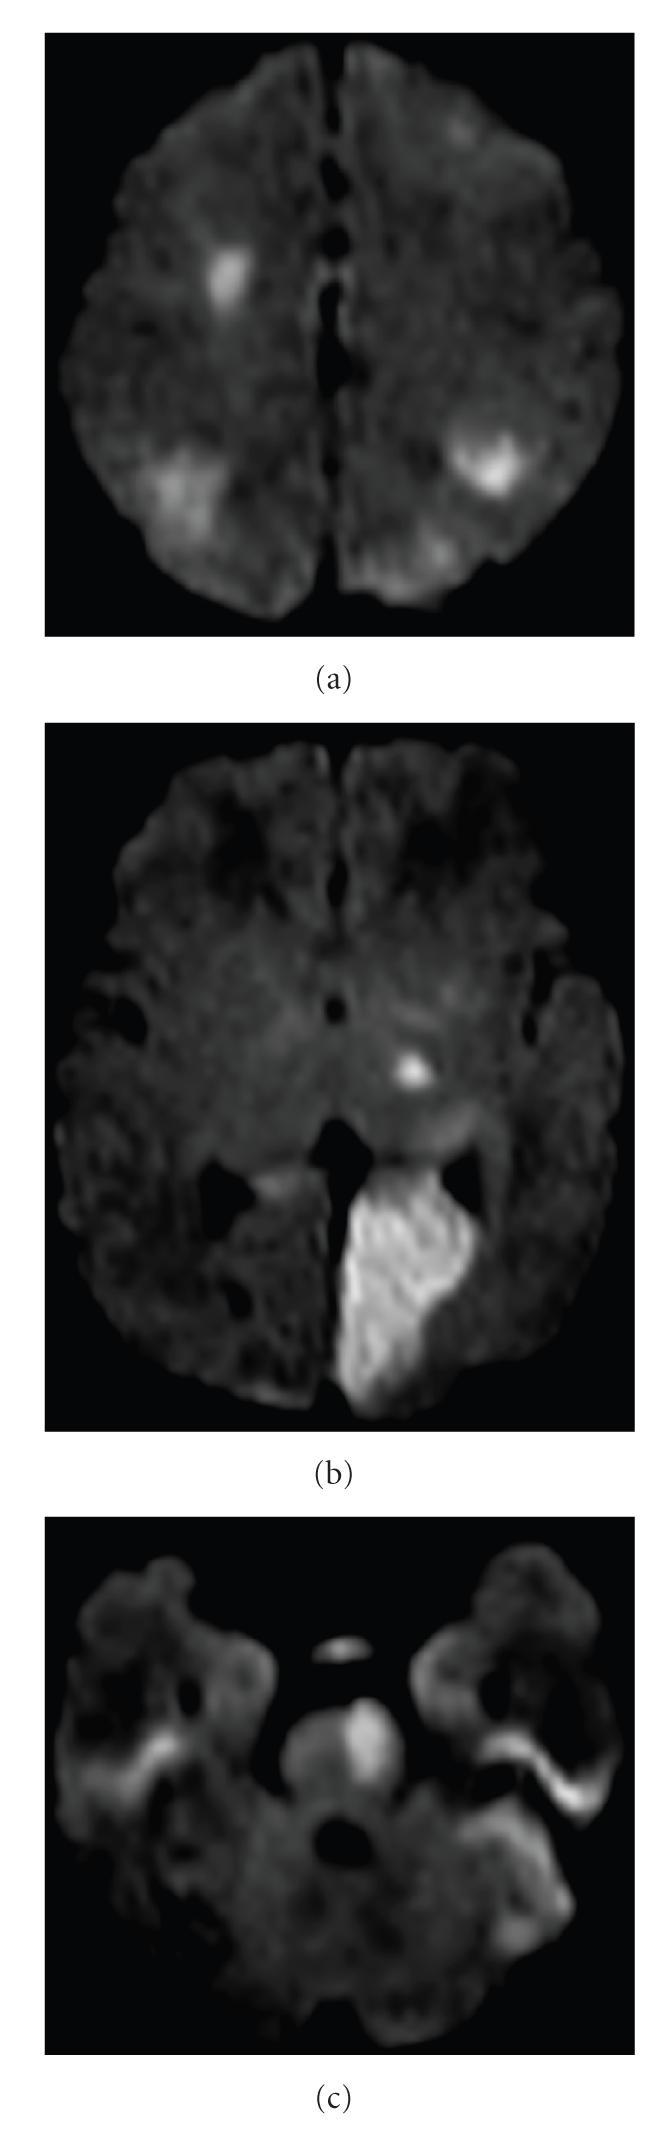

A full-term neonate suffered multifocal cerebral infarctions due to multiple large vessel thrombi. Thrombophilia and cardiovascular assessments were negative, but due to the severity of the lesions and the concern for expansion of the thrombi or future embolic events, treatment with low-molecular-weight heparin (LMWH) was initiated. No complications from treatment were experienced. We present this severe case in order to highlight difficult management decisions for newborns with multifocal perinatal thromboembolic stroke and to stress the need for further practice guidelines and research in this area.